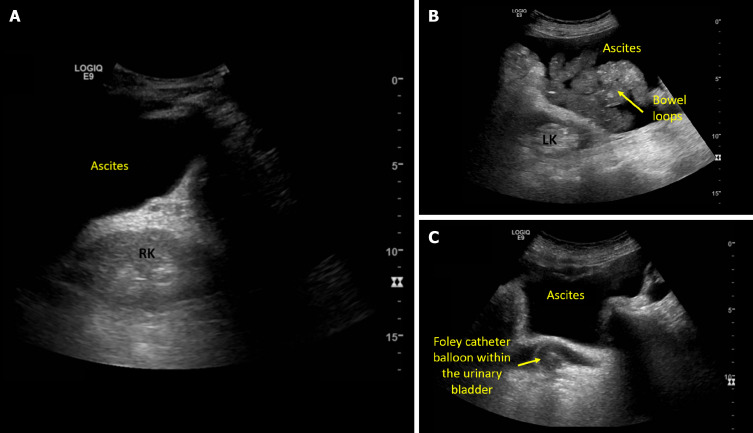

Discerning the etiology of acute kidney injury (AKI) in cirrhotic patients remains a formidable challenge due to diverse and overlapping causes. The conventional approach of empiric albumin administration for suspected volume depletion may inadvertently lead to fluid overload. In the recent past, point-of-care ultrasonography (POCUS) has emerged as a valuable adjunct to clinical assessment, offering advantages in terms of diagnostic accuracy, rapidity, cost-effectiveness, and patient satisfaction. This review provides insights into the strategic use of POCUS in evaluating cirrhotic patients with AKI. The review distinguishes basic and advanced POCUS, emphasizing a 5-point basic POCUS protocol for efficient assessment. This protocol includes evaluations of the kidneys and urinary bladder for obstructive nephropathy, lung ultrasound for detecting extravascular lung water, inferior vena cava (IVC) ultrasound for estimating right atrial pressure, internal jugular vein ultrasound as an alternative to IVC assessment, and focused cardiac ultrasound for assessing left ventricular (LV) systolic function and identifying potential causes of a plethoric IVC. Advanced POCUS delves into additional Doppler parameters, including stroke volume and cardiac output, LV filling pressures and venous congestion assessment to diagnose or prevent iatrogenic fluid overload. POCUS, when employed judiciously, enhances the diagnostic precision in evaluating AKI in cirrhotic patients, guiding appropriate therapeutic interventions, and minimizing the risk of fluid-related complications.